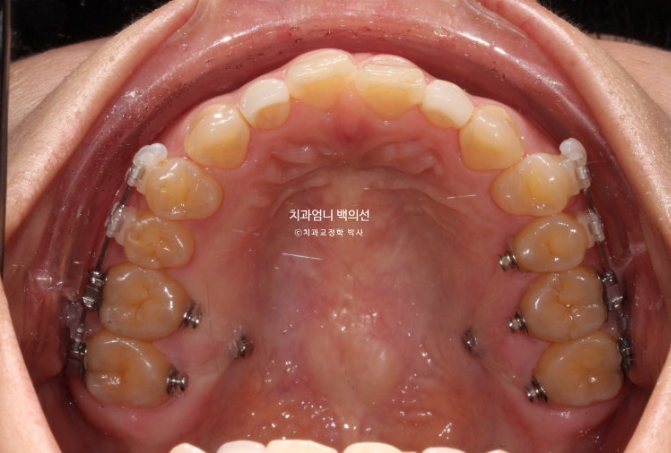

24.10

치료시작으로부터 1년 5개월 후 모습입니다. 먼저 위 장치 다 떼고 피팅준비를 합니다.

사진에서 보듯이 어금니가 잇몸에 파묻히기 직전까지 함입을 시켰으니 이제 남은 개방교합은 앞니쪽에서 해결을 봐야죠. 이때부터 앞니를 정출시키기 위해 클리피씨 장치를 위아래 모두 부착했습니다.

어금니 합입기간동안 앞니에는 장치를 붙이지 않습니다. 그래야 클리피씨 장치 붙이는 기간을 최소화 할 수 있고 환자분도 편합니다.